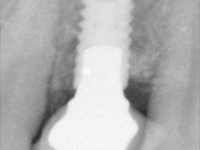

Paciente do sexo feminino, com 47 anos não fumadora. Apresentou-se na consulta com o dente 1.3 com tratamento endodôntico e com um espigão falso coto fundido, reabilitado com uma coroa provisória. Os dois incisivos laterais superiores são conoides e de reduzida dimensão. O dente 2.2 apresenta mobilidade, consentânea com uma significativa reabsorção óssea entre o dente 2.1 e o dente 2.3 Os dois incisivos centrais estão separados por um diastema de 3mm e o dente 2.3 apresenta uma oclusão cruzada com o dente antagonista. Verifica-se também a ausência de alguns dentes posteriores e uma higiene oral razoável. Na segunda intervenção realizada passados 8 anos, verificou-se que os incisivos centrais superiores se apresentavam cromaticamente mais escuros e apresentavam um sulco longitudinal no esmalte que estando pigmentado comprometia esteticamente o sorriso. O trabalho realizado na primeira fase do tratamento mostrava-se competente estética e funcionalmente. Por fim, um ano após a última intervenção, a paciente apresentou-se com uma fratura da faceta colocada no dente 2.1 provavelmente em resultado de estar em contacto com o coto do implante. A rigidez da anquilose implantar, pode ter sido a causa desta fratura. Outros casos deste tipo de fratura já foram observados por mim em situações clínicas idênticas. A faceta do dente 1.2 apresentava-se esteticamente comprometida e a própria estrutura dentária apresentava uma pequena cárie e, pelo que se recomendaria a sua substituição.

• Colocação de um Implante no local do dente 2.2. Reabilitação do implante com um “abutment” de componente coronário e gengival. em que o orifício de acesso ao parafuso fosse “camuflado” com uma faceta feldspática.

O tratamento iniciou-se com a re -preparação do coto do espigão falso coto fundido, com o objetivo de colocar as linhas de acabamento cervical com uma localização intra-sulcular e simultaneamente confecionar uma coroa provisória adaptada. Com um tratamento ortodôntico muito simples, fechou-se o diastema entre os incisivos centrais superiores e estabilizou-se esta posição com um arame colocado na superfície palatina dos centrais, funcionando como contenção. Posteriormente procurou-se fazer uma tração ortodôntica lenta do dente 2.2 com o intuito de diminuir, ainda que muito ligeiramente a perda óssea vertical nessa zona. Finalizada a tração, foi feita a extração do dente 2.2 e a zona foi reabilitada provisoriamente com uma coroa de resina composta colada aos dentes adjacentes. Foi colocado um implante dentário na zona do dente 2.2 sendo novamente colada a coroa provisória em resina, reabilitando provisoriamente a paciente durante o período de osseointegração. No dente 1.3 foi feita uma gengivectomia com bisturi elétrico, com a intenção de subir o nível cervical do 1.3 conseguindo uma maior harmonia com o dente 2.3. Estabilizados os tecidos moles, foi feita uma impressão com a técnica de moldeira aberta, utilizando silicones de adição de consistência “putty” e “light”. A recolha da cor, tanto da componente dentária como dos tecidos moles foi feita pelo ceramista no consultório.  No laboratório as impressões foram passadas a gesso e deram origem a modelos de trabalho que foram devidamente analisados. Foi decidido confecionar um “abutment” metalo-cerâmico aparafusado sobre o implante. Este “abutment” foi fundido com uma liga nobre e posteriormente revestido a cerâmica coronária e gengival. Dada a inclinação do implante o aparafusamento condicionou de forma inevitável a saída do orifício do parafuso pela superfície vestibular. No sentido de esconder esta situação, o desenho do “abutment” já foi idealizado com a intenção de acomodar na superfície vestibular a colagem de uma faceta feldspática. Este “abutment” foi provado em boca e foram feitos ajustes no componente cerâmico gengival. A sua adaptação aos tecidos moles foi feita tanto de forma subtrativa, com broca, como de forma aditiva, acrescentando resina composta de tonalidade gengival. Este acrescento de resina seria orientador do ceramista na colocação final da cerâmica de tonalidade gengival. A coroa que reabilitaria o dente 1.3 foi cimentada nesta consulta de prova com cimento de ionómero de vidro reforçado com resina composta. Finalizado o trabalho em laboratório da faceta sobre o 1.2 e o “abutment” e a faceta para o implante este foi colado em boca, após a colocação do isolamento absoluto. O trabalho satisfez plenamente a paciente. Durante oito anos a paciente foi seguida regularmente, mostrando-se agradada com o tratamento efetuado, no entanto começou a mostrar interesse em intervir esteticamente nos incisivos centrais superiores. Decidida a segunda fase da nossa intervenção, foi feita a preparação dentária dos dentes 1.1 e 2.1 para a colocação de duas facetas feldspáticas. Particular cuidado foi tido na preparação inter-proximal distal junto ao “abutment” do implante. Foi preciso avaliar muito pormenorizadamente o eixo de inserção da faceta em relação ao “abutment”. As facetas feldspáticas foram confecionadas em laboratório e posteriormente coladas em boca após a colocação de isolamento absoluto. Um ano após, iniciamos a nossa terceira fase de tratamento, após a faceta colada no dente 2.1 ter fraturado. A preparação dentária foi feita sobre a faceta colada, procurando estender mais para palatino o interface inter-proximal distal. O objetivo seria passar para mais palatino do ponto de contacto o interface faceta-dente. O preparo dentário do dente 1.2 também foi muito reduzido, limitando-se a criar um eixo de inserção. Após confecionadas a coroa total e a faceta em laboratório foram coladas em boca. Primeiro foi colada a coroa utilizando-se um isolamento relativo com teflon, posteriormente foi colada a faceta após a colocação do isolamento absoluto. Na coroa utilizei este tipo de isolamento para evitar a utilização de grampos. Seria difícil de aplicar pela forma e dimensão do dente e agressivo para os tecidos moles. Após a colagem foi avaliada a integração oclusal do trabalho.